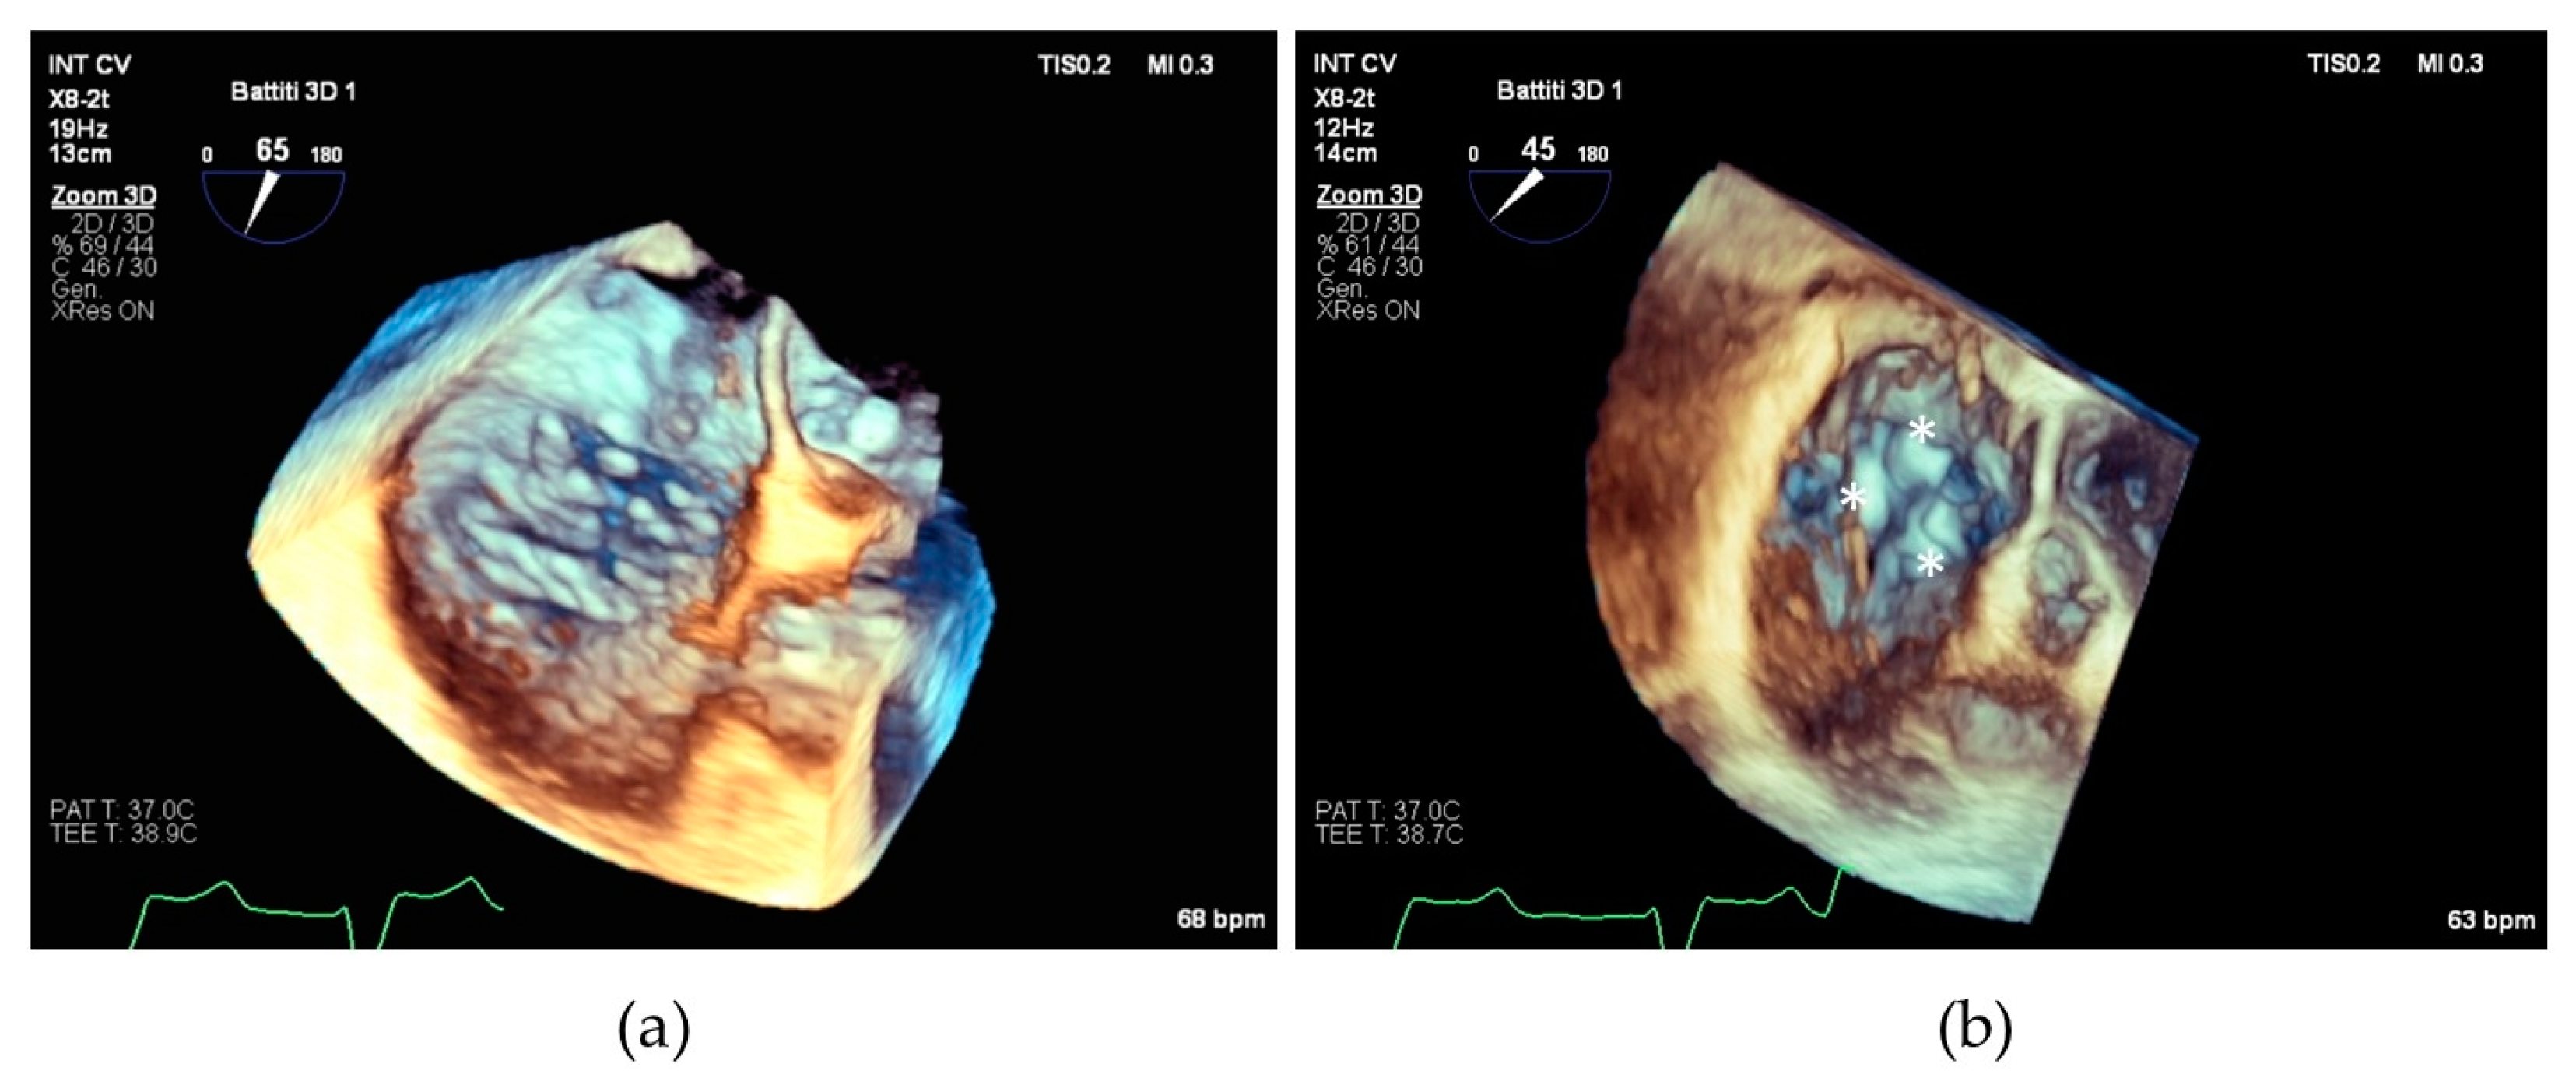

The SL-LAI was calculated by the sum of the lengths of septal and anterior leaflets normalized for the SL annulus diameter as previously described [16]. However, in our center experience, many patients treated with initial antero-septal grasping showed an intraprocedural persistence of significant TR and needed a second device implantation, often grasping the posterior leaflet. Therefore, we developed a novel modified leaflet-to-annulus index (LAI) derived from the sum of the anterior and posterior leaflets, normalized for the antero-posterior annulus diameter and we defined it as the AP-LAI (see Figure 1).

Figure 1. (a) Drawing showing tricuspid valve annulus and leaflets and the measures of antero-posterior diameter (red dotted line) and septal–lateral diameter (blue dotted line); (b) 3D transesophageal echocardiography with MPR reconstruction showing antero-posterior diameter measure (red) and anterior (green) and posterior (blue) leaflet measurement for computing the antero-posterior leaflet-to-annulus index; (c) 2D transesophageal echocardiography with orthogonal cross-section view showing the measure of septal–lateral diameter (red), septal (green) and anterior (blue) leaflet diameter for computing septal–lateral leaflet-to-annulus index; Abbreviations: Ant—anterior, AP—antero-posterior, Pos—posterior, Sep—septal, LA—left atrium, RA—right atrium, RV—right ventricle, SL—septal–lateral.